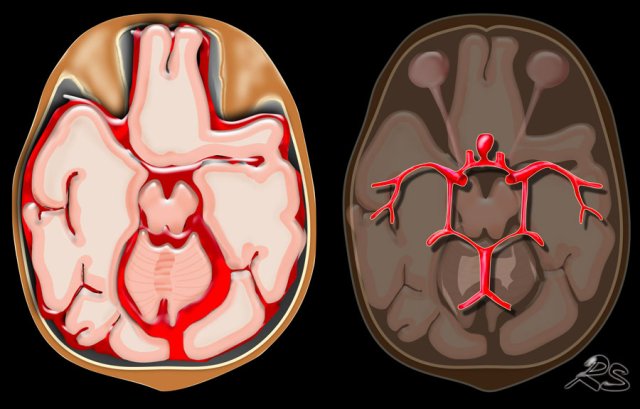

Knowing the location of a hemorrhage is often the key to the differential diagnosis especially in non-traumatic bleeding.

• Subarachnoid hemorrhage is acute bleeding under the arachnoid. Most commonly seen in rupture of an aneurysm or as a result of trauma.

• Lobar hematoma is located in the periphery of a lobe. The most common cause is cerebral amyloid angiopathy, but can also be seen in hypertension, tumor, vascular malformation, venous infarction and many other diseases.

• Centrally located hemorrhage in basal ganglia, pons or cerebellum. The most common cause is hypertension.

85% of non-traumatic hemorrhages are seen in patients with hypertension or cerebral amyloid angiopathy (CAA).

In hypertension the hemorrhages are typically in a central position in the basal ganglia, pons, thalamus and cerebellum, while in CAA they are typically more in a peripheral location - deep in the frontal, parietal or temporal lobes - also called lobar hemorrhages.